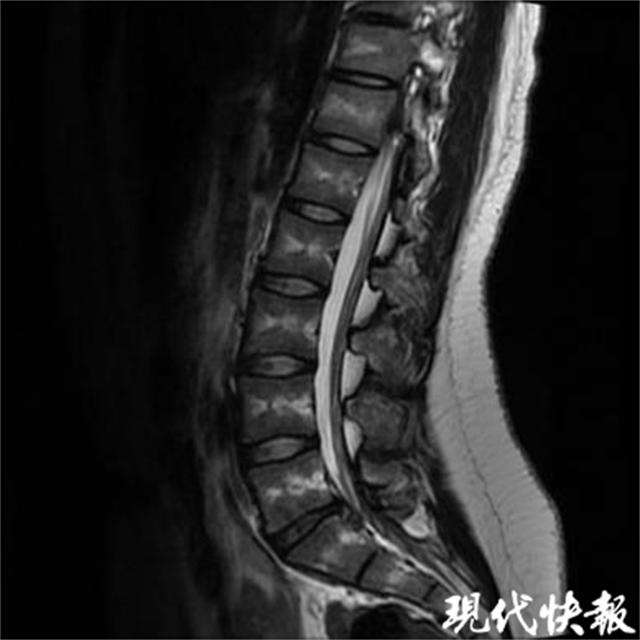

今年扬州的王同学 17 年纪大了,腰腿痛已经存在了 5 一个月,尤其是最近 2 在过去的几个月里,疼痛明显加重,导致学习能力和生活质量下降。这段时间,父母带他到处求医问药,最后被诊断为腰椎间盘突出症,采用保守疗法后效果不佳。后来经过亲朋好友的推荐,来到杜建伟门诊就诊。根据病人的病史、体征和影像检查,杜建伟指出这是 L5/S1 椎间盘突出压迫神经根引起腰腿痛等症状。经保守治疗,效果不佳,可进行微创手术。经过与病人及家属的充分沟通,最终决定采用微创手术来解决问题。

杜建伟帮助患者办理住院手续,第二天便完善了相关检查并进行了手术,手术十分顺利,手术切口仅约约。 5 mm。手术后,王的腰腿痛明显缓解,当天下午就可以下床了。杜建伟团队为他制定了详细的康复和随访计划,王第二天就出院了。